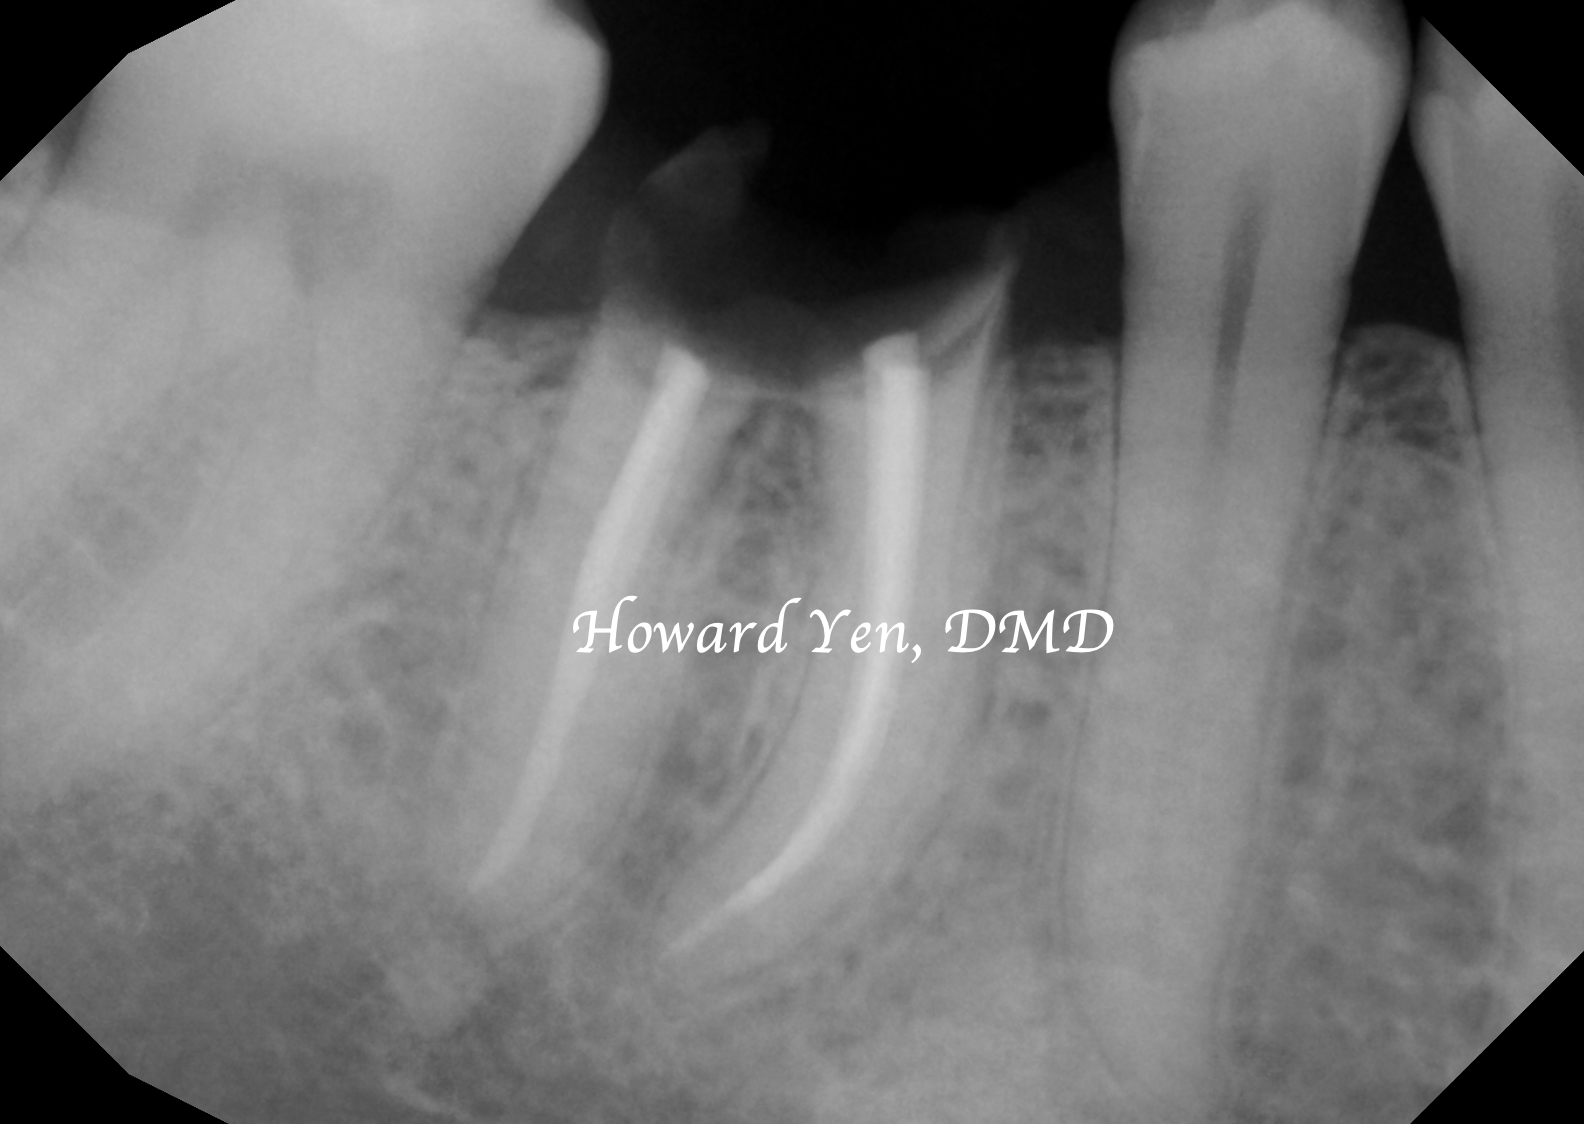

Once a natural tooth is removed from jaw bone, the jaw bone will undergo resorption (shrinkage) in volume. When there is a plan to replace the extracted tooth with dental implant, then there’s some treatment strategies to help reduce the rate of jaw bone shrinkage in order to provide adequate bone volume to receive dental implant. This procedure is often NOT necessary if there’s no plans to replace the tooth nor a strategic value (such as wisdom tooth extractions, the furthest molar in the mouth).